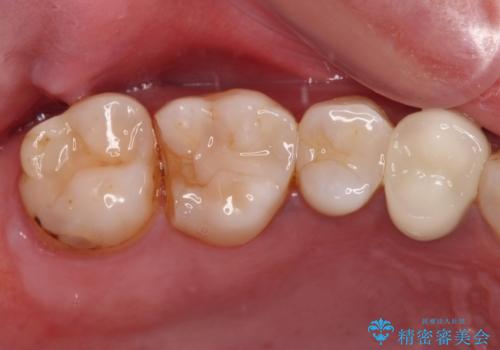

欠けてしまった奥歯 セラミッククラウンとセラミックインレーによるむし歯治療